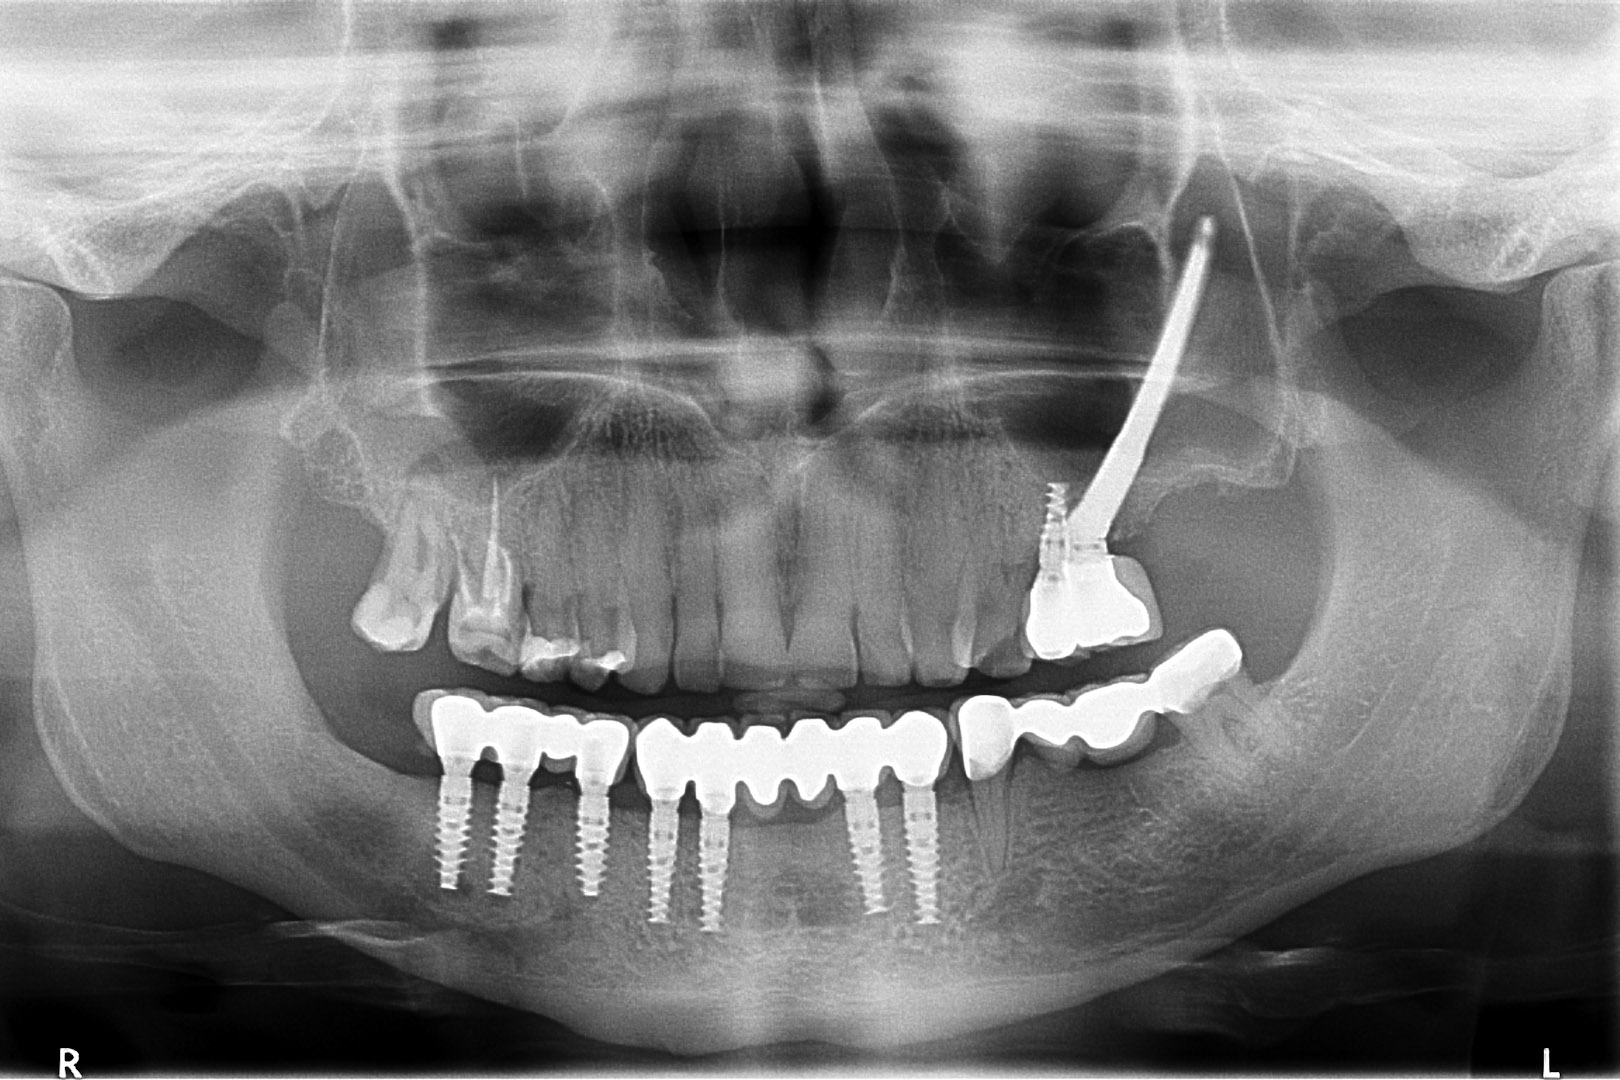

Przed podjęciem leczenia należy określić stopień zaniku kości szczęk oraz żuchwy. W tym celu przeprowadza się badanie kliniczne oraz odpowiednią diagnostykę obrazową pacjenta. Uwzględnia ona zdjęcie panoramiczne OPG jako podstawę dwuwymiarowego obrazowania podłoża kostnego oraz możliwe jest badanie tomograficzne CT lub bardziej precyzyjna tomografia stożkowa CBCT. Opcjonalnie wykorzystywana diagnostycznie tomografia pozwala na bardziej wnikliwą ocenę stopnia zaniku kości w trójwymiarowym, przestrzennym obrazie.

Procedury te są stosowane w sytuacji niedostatecznej ilości kości, skutkującej odsłonięciem gwintu, podczas gdy wszczepiamy implanty stomatologiczne lub też jako zabiegi poprzedzające ich wprowadzenie.​